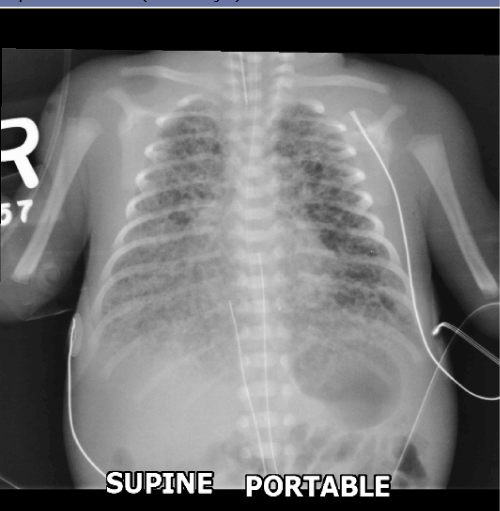

Newborn infant with respiratory distress.

DIagnosis and key xray findings.

Meconium aspiration.

Linear densities emanating from the hila and increased lung volumes.

Most common in term infants with in utero or intrapartum stress.